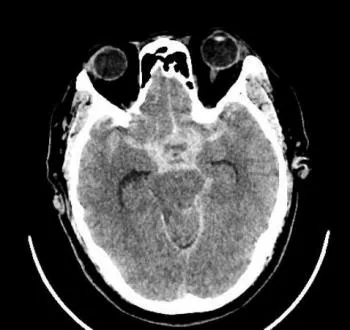

近日凌晨,峨眉山市人民医院急诊科接到内蒙古游客求救电话,55岁的鞠先生来峨眉旅游,突发剧烈头痛、呕吐,救护车随即出发,凌晨2点25分将患者接回医院,急诊头颅CT显示:大量蛛网膜下腔出血。神经外科副主任医师杨志敏立即前往急诊科会诊,根据多年丰富的临床经验,杨志敏医生判断患者为颅内动脉瘤破裂导致的蛛网膜下腔出血,急诊CTA影像结果提示:患者颅内前交通动脉及左侧大脑中动脉分叉处分别有9.5*7.7... |